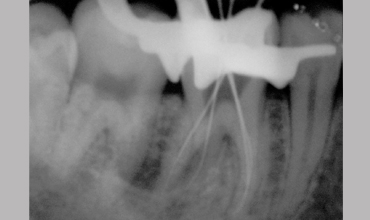

Management Of Radix Entomolaris In Mandibular First Molar